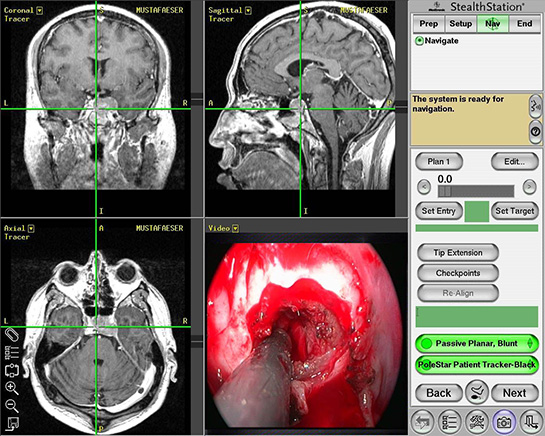

Bu evrelendirme, tedavi seçeneklerini ve prognozu belirlemede yardımcı olur. Grading (Derecelendirme)Grading, tümör hücrelerinin farklılaşma derecesini tanımlar. Düşük dereceli tümörler (G1), daha iyi farklılaşmış ve daha az agresifken, yüksek dereceli tümörler (G3) daha kötü farklılaşmış ve daha agresif olarak kabul edilir. Bu derecelendirme, tedavi stratejilerinin belirlenmesinde önemli bir faktördür. Moleküler Sınıflama Moleküler sınıflama, tümörlerin genetik ve biyolojik özelliklerine göre sınıflandırılmasını içerir. Bu sınıflama, tümörlerin moleküler profillemesi ile gerçekleştirilir ve bireyselleştirilmiş tedavi yaklaşımlarını desteklemek için kullanılır. Özellikle hedefe yönelik tedavilerin gelişimi açısından büyük önem taşımaktadır. Tümör Sınıflamasının Önemi Tümör sınıflaması, klinik karar verme süreçlerinde temel bir rol oynamaktadır. Bu sınıflama sayesinde:

Tümör sınıflaması, kanser tedavisinin temel taşlarından biridir ve her hastanın bireysel özelliklerine göre en uygun tedavi planının oluşturulmasında kritik bir öneme sahiptir. Sonuç Tümör sınıflaması, kanserin yönetiminde önemli bir araçtır. Histopatolojik, evrelendirme, derecelendirme ve moleküler sınıflama gibi çeşitli yöntemler kullanılarak, tümörlerin doğru bir şekilde değerlendirilmesi sağlanmaktadır. Bu sistemlerin etkin bir şekilde kullanılması, hastaların tedavi süreçlerinin optimize edilmesine ve yaşam kalitelerinin artırılmasına yardımcı olmaktadır. |